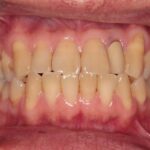

「年齢のせい」とあきらめない

お口の衰え対策

口腔機能低下症は、加齢や生活習慣などにより、噛む力・飲み込む力・舌や唇の動きが少しずつ低下していく状態です。

自覚しにくいことも多く、「気づいたときには食事がつらくなっていた」というケースも少なくありません。

食事中にむせやすい

食べこぼしが増えた

会話中に滑舌が悪くなった